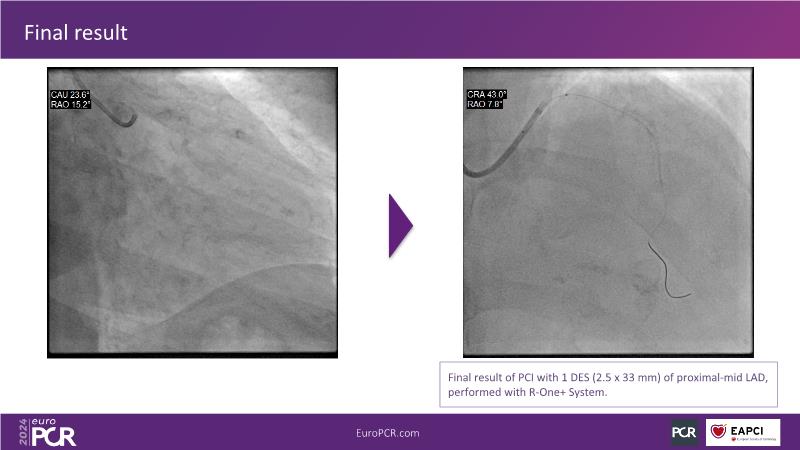

In this session, discover the effectiveness and safety of robotic PCI for both simple and complex lesions requiring additional devices like IVL, IVUS, laser, and FFR. Learn about the numerous benefits of robotics for patients and cathlab teams, including enhanced precision in wire navigation and stent positioning, full radioprotection, and reduced orthopedic injuries. Explore the growing interest in robotics within the interventional cardiology community, anticipate future technical advancements, and understand how AI will accelerate the integration of robotics and vice versa.